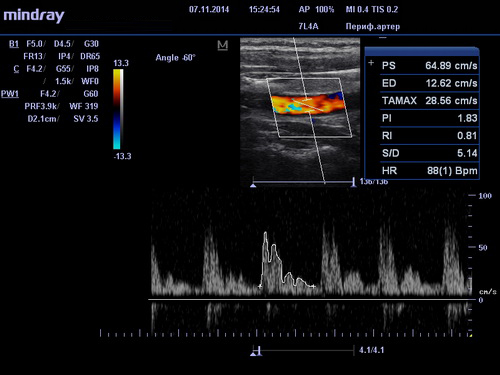

УЗИ сосудов в клиниках DoktorRU проводится по технологии, за основу которой взят эффект Допплера. Его суть заключается в том, что о состоянии и положении объекта можно судить по ширине волны, исходящей от него при движении. Это открытие дало возможность исследовать такие мельчайшие объекты как кровяные тельца в движении. УЗИ сосудов при использовании допплерометрии (или как ее еще называют, Допплерографии) позволяет получать очень точную информацию о состоянии кровеносных сосудов и на ее основе выявлять заболевания даже на ранних, досимптомных стадиях. Поэтому УЗИ сосудов объективно можно считать важнейшим инструментом диагностики и профилактики сердечно-сосудистых заболеваний.